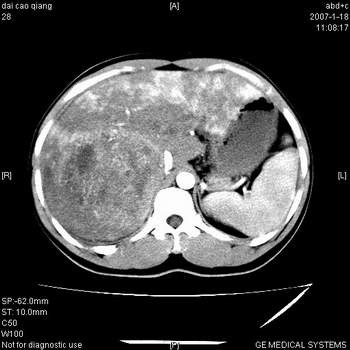

符合巨块型肝癌表现:

1、平扫低密度,增强后表现为快进快出。

2、动脉期可见迂曲的动脉供血血管

3、并可见门静脉右支癌栓形成

4、可见假包膜

5、腹主动脉旁结节影,考虑肿大淋巴结。

肝右叶巨大不均匀低密度肿块,前缘有假包膜,增强明显的呈快进快出表现,门脉右支有癌栓,病人虽然年轻但还是首先考虑肝右叶巨块形肝癌,病人血象高只能说有合并感染。不支持肝脓肿。